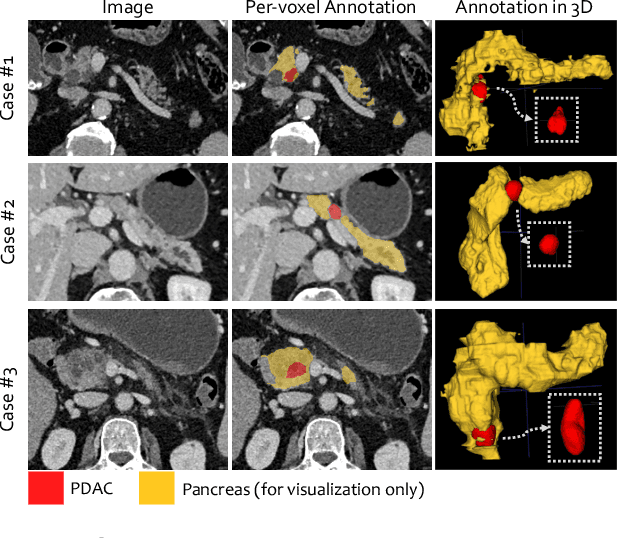

Abstract:Pancreatic ductal adenocarcinoma (PDAC) is the third most common cause of cancer death in the United States. Predicting tumors like PDACs (including both classification and segmentation) from medical images by deep learning is becoming a growing trend, but usually a large number of annotated data are required for training, which is very labor-intensive and time-consuming. In this paper, we consider a partially supervised setting, where cheap image-level annotations are provided for all the training data, and the costly per-voxel annotations are only available for a subset of them. We propose an Inductive Attention Guidance Network (IAG-Net) to jointly learn a global image-level classifier for normal/PDAC classification and a local voxel-level classifier for semi-supervised PDAC segmentation. We instantiate both the global and the local classifiers by multiple instance learning (MIL), where the attention guidance, indicating roughly where the PDAC regions are, is the key to bridging them: For global MIL based normal/PDAC classification, attention serves as a weight for each instance (voxel) during MIL pooling, which eliminates the distraction from the background; For local MIL based semi-supervised PDAC segmentation, the attention guidance is inductive, which not only provides bag-level pseudo-labels to training data without per-voxel annotations for MIL training, but also acts as a proxy of an instance-level classifier. Experimental results show that our IAG-Net boosts PDAC segmentation accuracy by more than 5% compared with the state-of-the-arts.